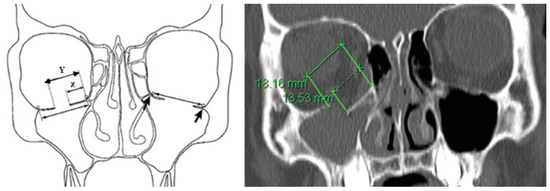

| CT Slice | X (mm) | Y (mm) |

| 15 | 0 | 0 |

| 16 | 8.1 | 12.3 |

| 17 | 9.3 | 13.1 |

| 18 | 13.5 | 18.2 |

| 19 | 7.6 | 14.8 |

| 20 | 3.1 | 11.8 |

| 21 | 0.2 | 9.6 |

| 22 | 0 | 4.5 |

| 23 | 0 | 2.0 |

| 24 | 0 | 0 |